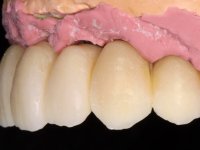

O paciente foi observado conjuntamente e a dúvida que surgiu de imediato foi se seria possível com a regeneração óssea a efectuar poder ser reabilitada naturalmente a zona das papilas interdentárias. Nesse sentido foi feito um enceramento de diagnóstico que contemplaria as duas hipóteses, utilizando ou não a cerâmica gengival. A confecção desse enceramento foi fundamental para expor ao paciente a dificuldade da reabilitação. O wax-up deu origem a um mock-up que foi aprovado pelo paciente e que simultaneamente serviu de guia imagiológica. O caso foi planificado cirurgicamente e realizada uma guia cirúrgica com que foram colocados os implantes. Após 10 semanas foi feita a 1ª impressão para confecção da ponte provisória. Foram criados os primeiros perfis de emergência na gengiva artificial e foi digitalizado o modelo. Por processo de CAD-CAM foi confeccionada uma ponte provisória aparafusada baseada no enceramento de diagnóstico. A ponte trabalhou durante 8 semanas os tecidos moles que foram fielmente copiados numa impressão com técnica de moldeira aberta. Os transferes foram individualizados com resina composta para copiarem fielmente os perfis de emergência criados pela ponte provisória. Confeccionado o modelo de trabalho definitivo, foi realizada uma infra-estrutura em zircónio seguindo a orientação do enceramento de diagnóstico. O assentamento da infra-estrutura foi testado em boca e simultaneamente foi novamente impressionados os tecidos moles com um silicone fluido. Nessa consulta foi feito o levantamento da cor. Os dentes 13 e 23 apresentavam uma saturação anormalmente forte que resolvemos não valorizar, optando por privilegiar a relação com o sector antero-inferior. Foi realizada uma nova gengiva artificial com a impressão que acompanhou a impressão de arrasto com a infra-estrutura. Após a colocação da cerâmica na infra-estrutura foram coladas as meso-estruturas. O trabalho final foi aparafusado lentamente permitindo a adaptação dos tecidos moles.